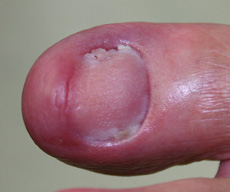

Nail Disorders – There are several different diseases that affect the nails, often as a result of a fungal or bacterial infection. Ingrown toenails are the most common nail ailment, involving the corners of the nails digging into the surrounding soft tissue, causing irritation and swelling. Fungal infections commonly affect the toenails (and sometimes the fingernails as well), as a result of exposure to a warm, moist environment, and cause thick, brittle and distorted nails.

Treatment for nail diseases may include oral or topical medications. The nail may need to be removed for severe infections. Patients can prevent nail conditions from developing by keeping the feet clean and dry, wearing shoes that fit well and clipping toenails straight across.